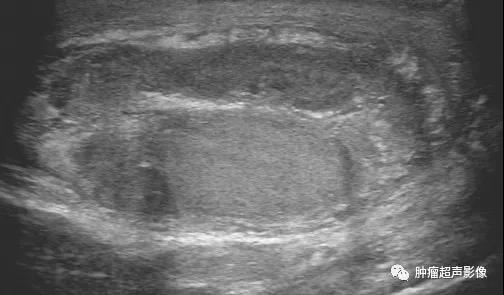

急性睾丸附睾炎:右侧附睾及睾丸回声不均,血流丰富,睾丸鞘膜腔积液